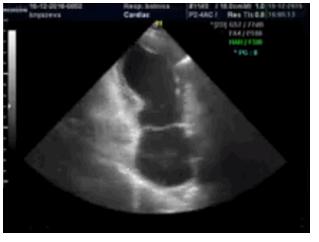

Несмотря на то что с помощью трансторакальной ЭхоКГ можно выявить нарушения регионарной сократимости ЛЖ, следует помнить, что получение истинного изображения верхушки сердца может быть затруднено, особенно у пациентов, нуждающихся в неотложной помощи.

Нередко диагноз стрессовой кардиомиопатии (СКМП устанавливают в операционной при выполнении вентрикулографии ЛЖ, поскольку обычно предполагают ОКС, по поводу которого назначают неотложную или экстренную коронарографию. Исследование ПЖ также позволяет выявить сходные нарушения регионарной сократимости миокарда примерно у 25% больных, у которых имеется тенденция к более тяжелому течению заболевания и более высокий риск застойной СН.